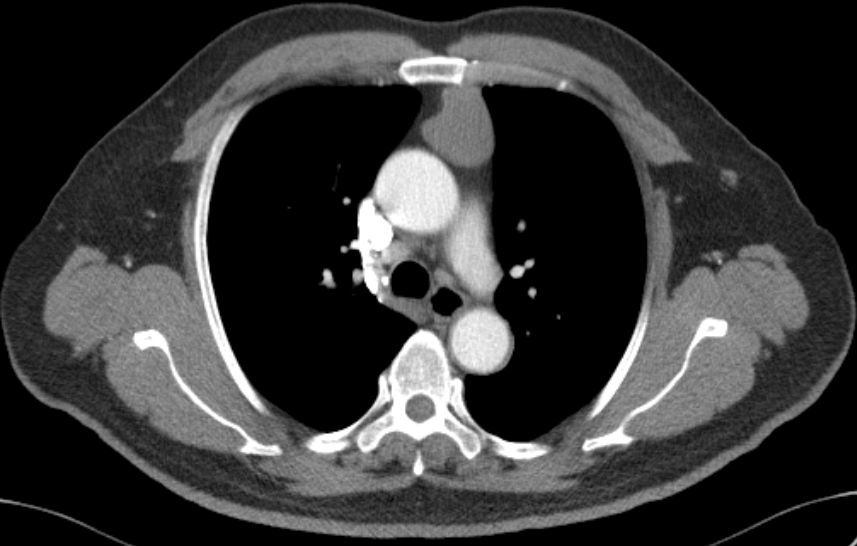

前纵隔结节前纵隔肿块胸腺囊肿thymiccyst和胸腺瘤如何区别需要手术吗